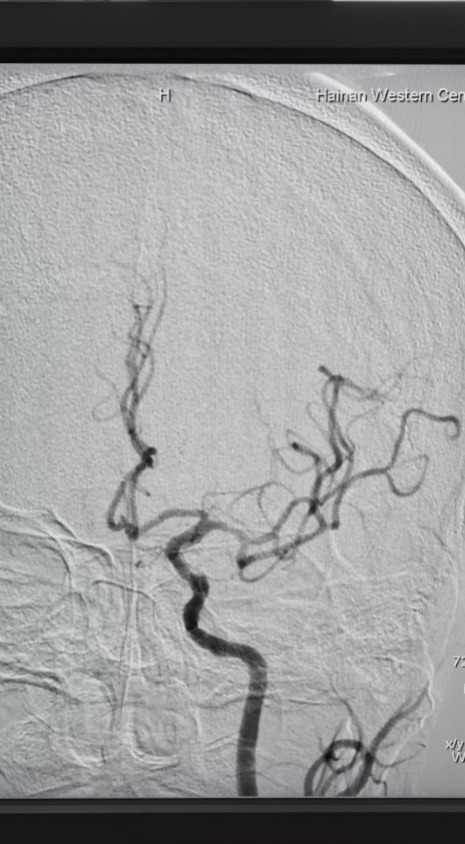

考虑到患者病情复杂、预期手术难度高、风险大,神经内科介入团队根据实际情况,为患者置入了全国首款maurora雷帕霉素药物洗脱支架。术后造影显示,其右侧椎动脉狭窄解除,脑供血不足明显改善,患者恢复良好。据悉,此次椎动脉药物洗脱支架置入术属我院首次开展,成功填补了海南西部地区脑血管介入治疗的空白。

术后DSA